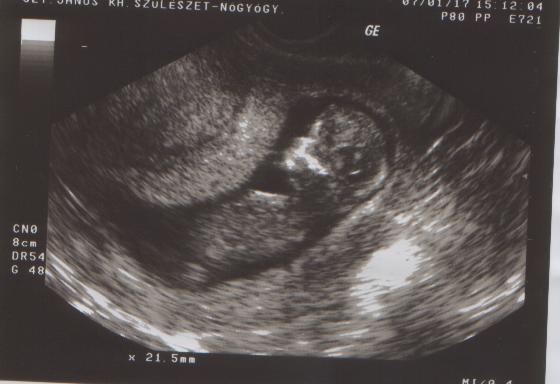

Gurgula, nagyon édes a babátok! Hol készült az uh kép? Magánrendelőbe.

Szóval, babuska nagyon cuki volt, ficánkolt, integetett, de leginkább a feje alá tett kézzel "héderezett" (Berci is mindig ezt csináta UH-n, azóta is így alszik...mint Apa). CRL: 54mm, NT:1mm, fejátmérő (nem tom a rövidítést): 21mm.